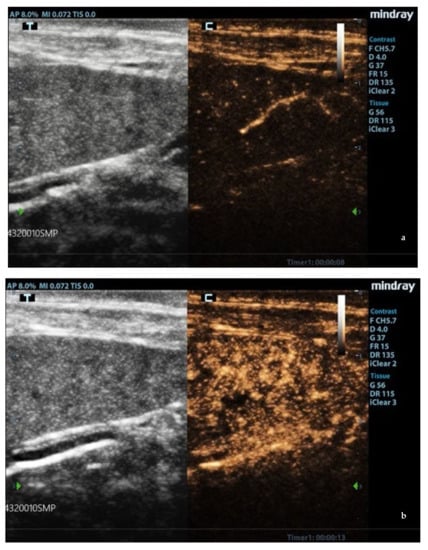

Ultrasound patterns of the spleen in L. infantum-infected dogs: (a) moth-eaten pattern and (b) marbled pattern. F: probe’s frequency; D: distance; G: gain; FR: frame rate; DR: dynamic range; AP: acoustic power; MI: mechanical index; TIS: tissue imaging specific; M9: ultrasound system. Green arrow: ultrasound focal point.

3.2. B-Mode Ultrasonography

Splenic enlargement was found in 11/22 (50%) leishmaniotic patients. Overall, 7/11 (63.6%) had diffuse parenchyma abnormalities, which were always accompanied by an increased size (Figure 1). Parenchyma had a moth-eaten appearance in 4/7 and a marbled appearance in 3/7. In the remaining four, spleen was subjectively reported to be of a larger size than normal but with a normal echotexture. A positive correlation with the clinical stage of disease was detected for splenic enlargement (r = 0.634; p = 0.036) and diffuse parenchymal alterations (r = 0.655; p = 0.047). The correlation between ultrasonographic alteration and splenic quantitative PCR showed a low positive effect (r = 0.06; p = 0.779). Conversely, there was no correlation between spleen enlargement and echotexture with lymph node parasite load (r = 0.26; p = 0.573, r = −0.329; p = 0.4705, respectively) and IFAT title (r = 0.33, p = 0.1413, r = −0.38; p = 0.09, respectively). In none of the three dogs negative for L. infantum were splenic enlargement or abnormalities of echotexture detected. Upon CPD examination, flow signals were detected in both normal appearance and in moth-eaten and marbled spleens; under careful observation, CPD frames in moth-eaten spleens showed the absence of flow in the more visible hypoechoic foci (Figure 2).